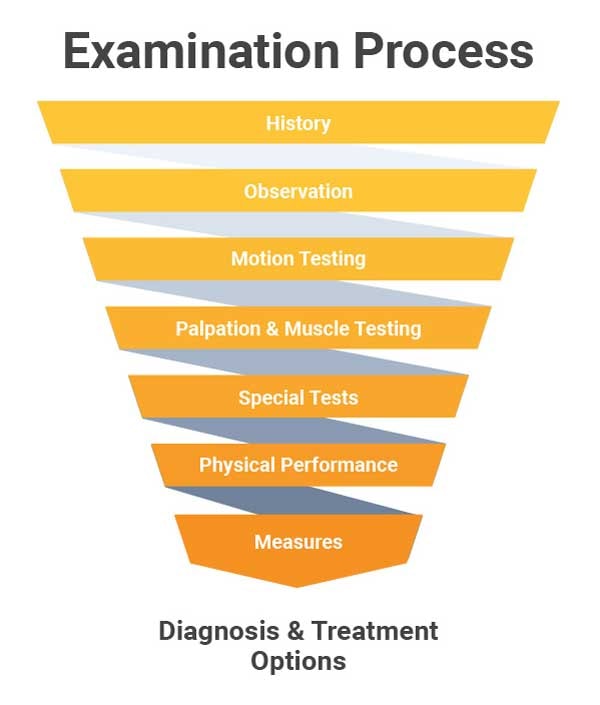

The Place of Special Tests in the Exam Process

The examination process includes many steps that ultimately result in providing you with a diagnosis and appropriate treatment options. Using special tests with good sensitivity, specificity, and likelihood ratios provide quality data to confirm and/or refute your diagnostic hypotheses. Good data from these tests allow you to determine appropriate treatment options and provide correct prognostic information to your patient.1

An SMP is the application of an outside force which changes a movement pattern or muscle activation pattern in order to reduce the severity of a patients symptoms with a particular activity. Even with asymptomatic movements, application of an SMP can improve the quality of a motion or the overall range of motion. This can be applied early on in the motion testing portion of the examination process.